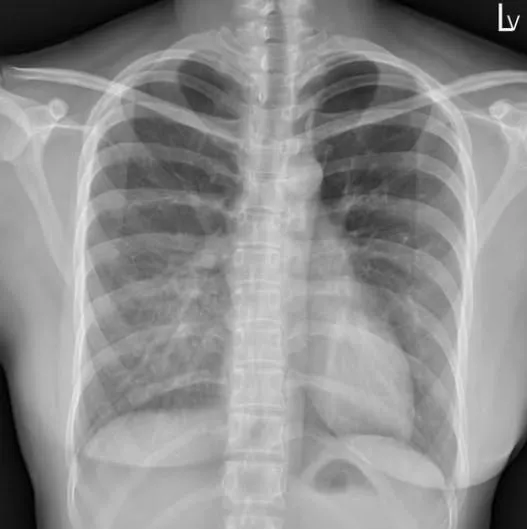

「肺看起來變白」不是肺炎!醫揭:漏斗胸關鍵在肋骨角度

漏斗胸

X光

肺炎

胸部X光